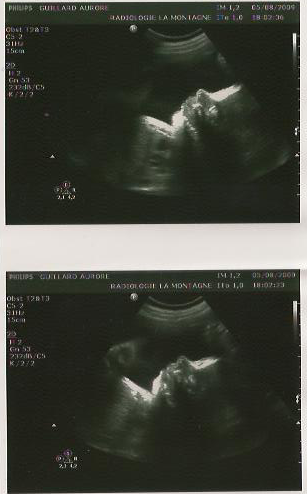

dernière échographie.

maiwenn

et on se dit que c’est énorme le changement entre la première et la dernière.

il y a 7 mois, on contrôlais que je soit bien enceinte, et on apercevait une petite bulle noire avec un haricot dedans

et là une grosse tête des gros pieds un gros ventre…. c’est énorme!

la différence entre ces deux clichets est de 7 mois, mais la différence est flagrante!

enfin bref tout va bien!

2 kg d’amour dans le ventre, confirmation c’est bien une petite bigouden, petits pieds et petites mains bien visible, tout petit nez qui me fait pensé à celui du papa 🙂 c’était encore un moment super agréable 🙂

seul bémol, la petite est en siège….  donc encore une échographie de prévu dans 3 semaines  pour contrôlé si elle c’est mise en position qui faciliterais les choses.